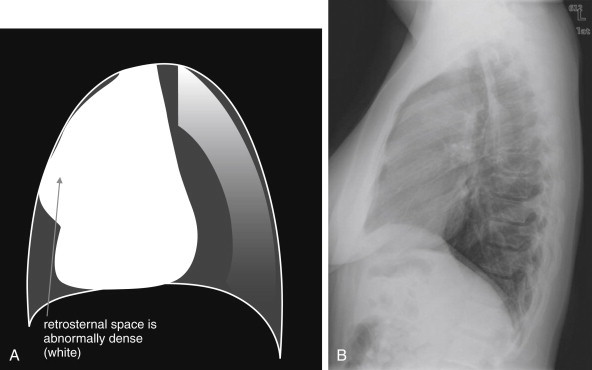

Lateral Upright Chest X-ray View: Retrosternal Space, Retrocardiac Space, and the Spine Sign

The lateral chest x-ray provides important diagnostic information. Unfortunately, this view is usually not obtained when a portable x-ray examination is performed—another good reason to send the patient to the radiology suite for imaging if the clinical condition permits this. The lateral view (Figure 5-16 ) reveals the retrosternal space, which overlies the heart and mediastinum on a frontal projection. This space is usually quite lucent (black) because of the presence of a low-density epicardial fat pad and sometimes lung segments—but when occupied by a soft-tissue mass, this space may appear radiodense (white) (Figure 5-17 ). The lateral chest x-ray also reveals the retrocardiac space. This space normally should be quite lucent (black) (see Figure 5-16). Lower lobe pneumonias may be evident on the lateral view as an abnormally dense retrocardiac region (Figure 5-18 ). On the lateral view, the diaphragms usually form smooth curves descending from anterior to posterior. The space above the diaphragms is usually lucent (black), as it contains low-density lung tissue. Pleural effusions may be evident on lateral view as dense (white) layering opacities replacing the normal curve of the diaphragm in this space (see Figure 5-9). Sometimes pleural effusions form a meniscus against the posterior wall of the thorax, actually reversing the normal curve of the diaphragm. In addition, air beneath the diaphragm (pneumoperitoneum) may be visible on the lateral view (see Figure 5-14).

The normal lateral chest x-ray shows progressive lucency (darkening) of the thoracic spine as it approaches the diaphragm. This normal finding is called the “spine sign.” Failure of the spine to become progressively more lucent as it approaches the diaphragm suggests an overlying opacity such as an infectious infiltrate or pleural effusion. The retrocardiac space should appear lucent (dark) as well, and the posterior diaphragmatic recess is dark and deep. The retrosternal space should be lucent (dark). A, A schematic representation. B, A patient with a normal spine sign and retrosternal and retrocardiac spaces.

Figure 5-17.

Abnormal retrosternal space, suggesting anterior mediastinal mass.

The abnormal lateral chest x-ray shows loss of the normal lucent retrosternal space. This abnormality is easily missed but indicates soft-tissue density in the anterior mediastinum. The differential diagnosis includes the five terrible Ts: thyroid mass (goiter or malignancy), thymoma, teratoma, “terrible” lymphoma, and thoracic aortic aneurysm. A, A schematic representation. B, A patient with a retrosternal density, suggesting anterior mediastinal mass.